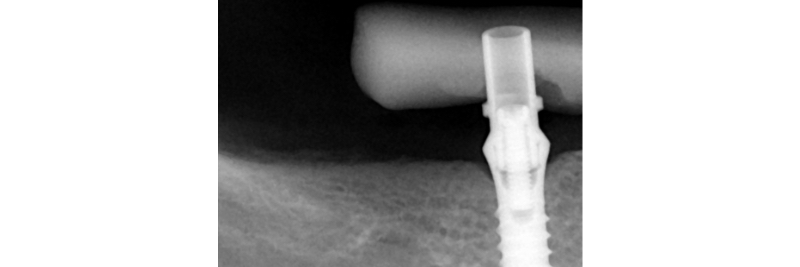

Radiographic verification of the temporary cylinder fully seated on the implant platform.